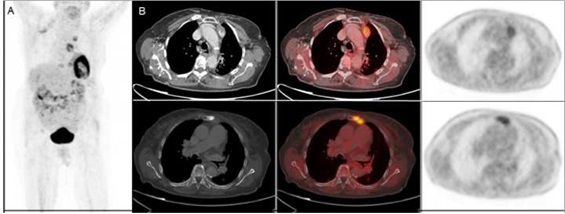

Mujer de 89 años diagnosticada de carcinoma mucinoso de mama izquierda estadio IIB (T2 N1 M0), tratado con cirugía más linfadenectomía axilar. Histológicamente, existía estroma mucoide en el tumor y sustitución masiva metastásica mucosecretora en ganglios axilares. Tras la radioterapia continúa seguimiento con remisión completa. A los seis años presenta elevación del antígeno carcinoembrionario (CEA), astenia y dolor en dorso. Es remitida al Servicio de Medicina Nuclear para descartar afectación ósea secundaria. La gammagrafía con 99mTc-HDP presenta un depósito en el esternón sugerente de malignidad y otro foco paraaórtico izquierdo, de difícil caracterización. El SPECT-TC de tórax localizó correctamente la captación sobre un nódulo mediastinal (fig. 1). Posteriormente, se realizó un PET-TC con 18F-FDG para re-estadificación, evidenciando compromiso metastásico óseo y ganglionar mediastinal (fig. 2).